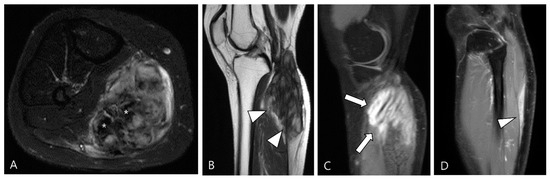

3.2. Differential Diagnoses of Extra-Articular D-TSGCT

3.2.2. Extra-Abdominal Desmoid-Type Fibromatosis (DF)

3.2.3. Tophaceous Gout